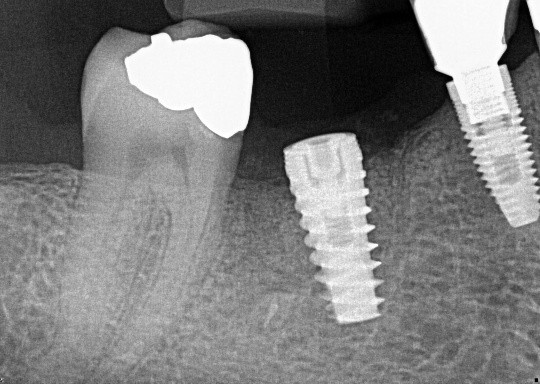

Tooth 4.8 is planned for extraction. Which radiographic findings suggest an increase in the degree of difficulty of the extraction?

13. (Select ONE OR MORE correct answers.)

Tooth 1.8 is planned for surgical extraction. Which radiographic findings suggest an increase in the degree of difficulty of the extraction?

Tooth 2.8 is planned for surgical extraction. Which radiographic findings suggest an increase in the degree of difficulty of the extraction?